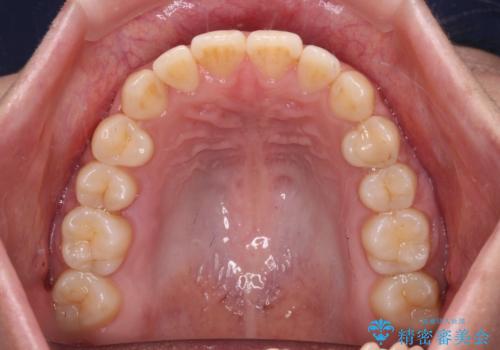

前歯のクロスバイト 目立たないワイヤー装置で速やかに矯正治療

治療前にお伝えした治療期間は1~1年半でして、1年4か月の期間で終えることができました。

ワイヤー矯正は見た目や装置が当たることでの痛みを気にされる方が多いですが、月1回来院して処置をしてもらうだけで歯並びが整うため、大変お勧めです。